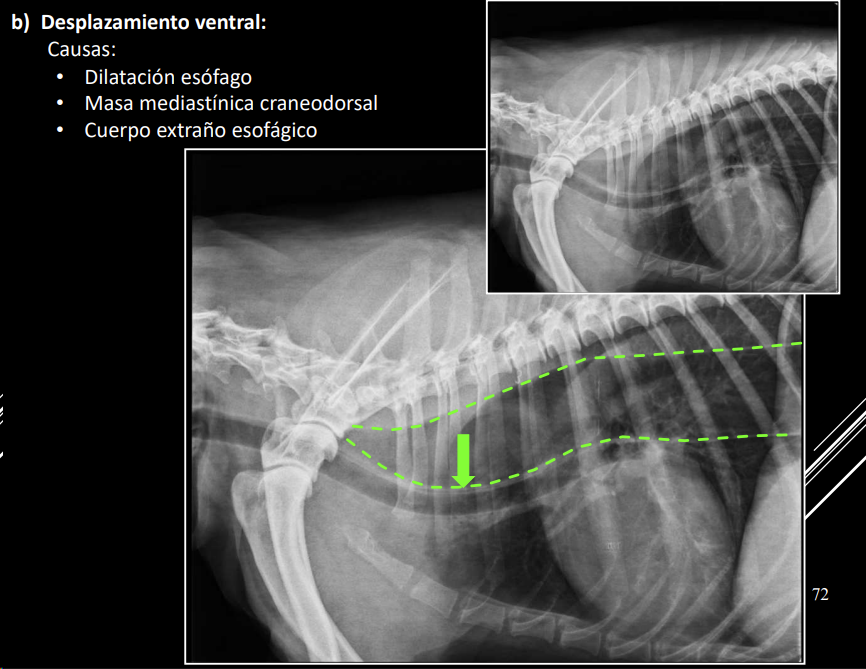

- Desplazamientos (dorsal o ventral).

- Dorsal: cardiomegalia, masa craneoventral.

- Ventral: dilatación esofágica, masa craneodorsal.